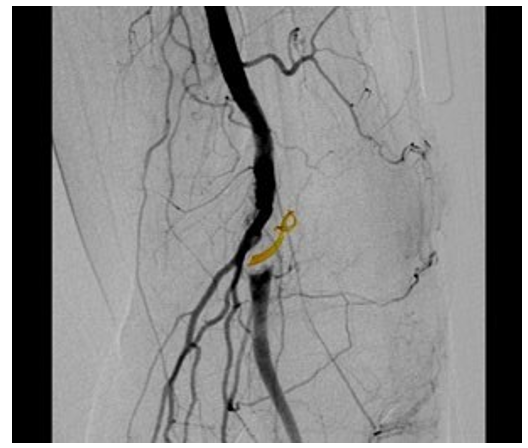

Case 2: A 64 years old sportsman was admitted to our institution with 1-month history of left calf intermittent claudication. Phys- ical examination revealed only a good left femoral pulse. Color Doppler ultrasonography showed sudden focal occlusion of a dilatated popliteal artery with poorly detectable distal flow. Hy- pertension was the only atherosclerotic risk factor. Patient un- derwent digital subtraction angiography (DSA) which showed perfect patency of all below the knee vessels and the “scimitar sign” at the popliteal level Figure 4.

Figure 4: Angiography showing the typical curvilinear scimitar sign due to extrinsic compression of the lumen.